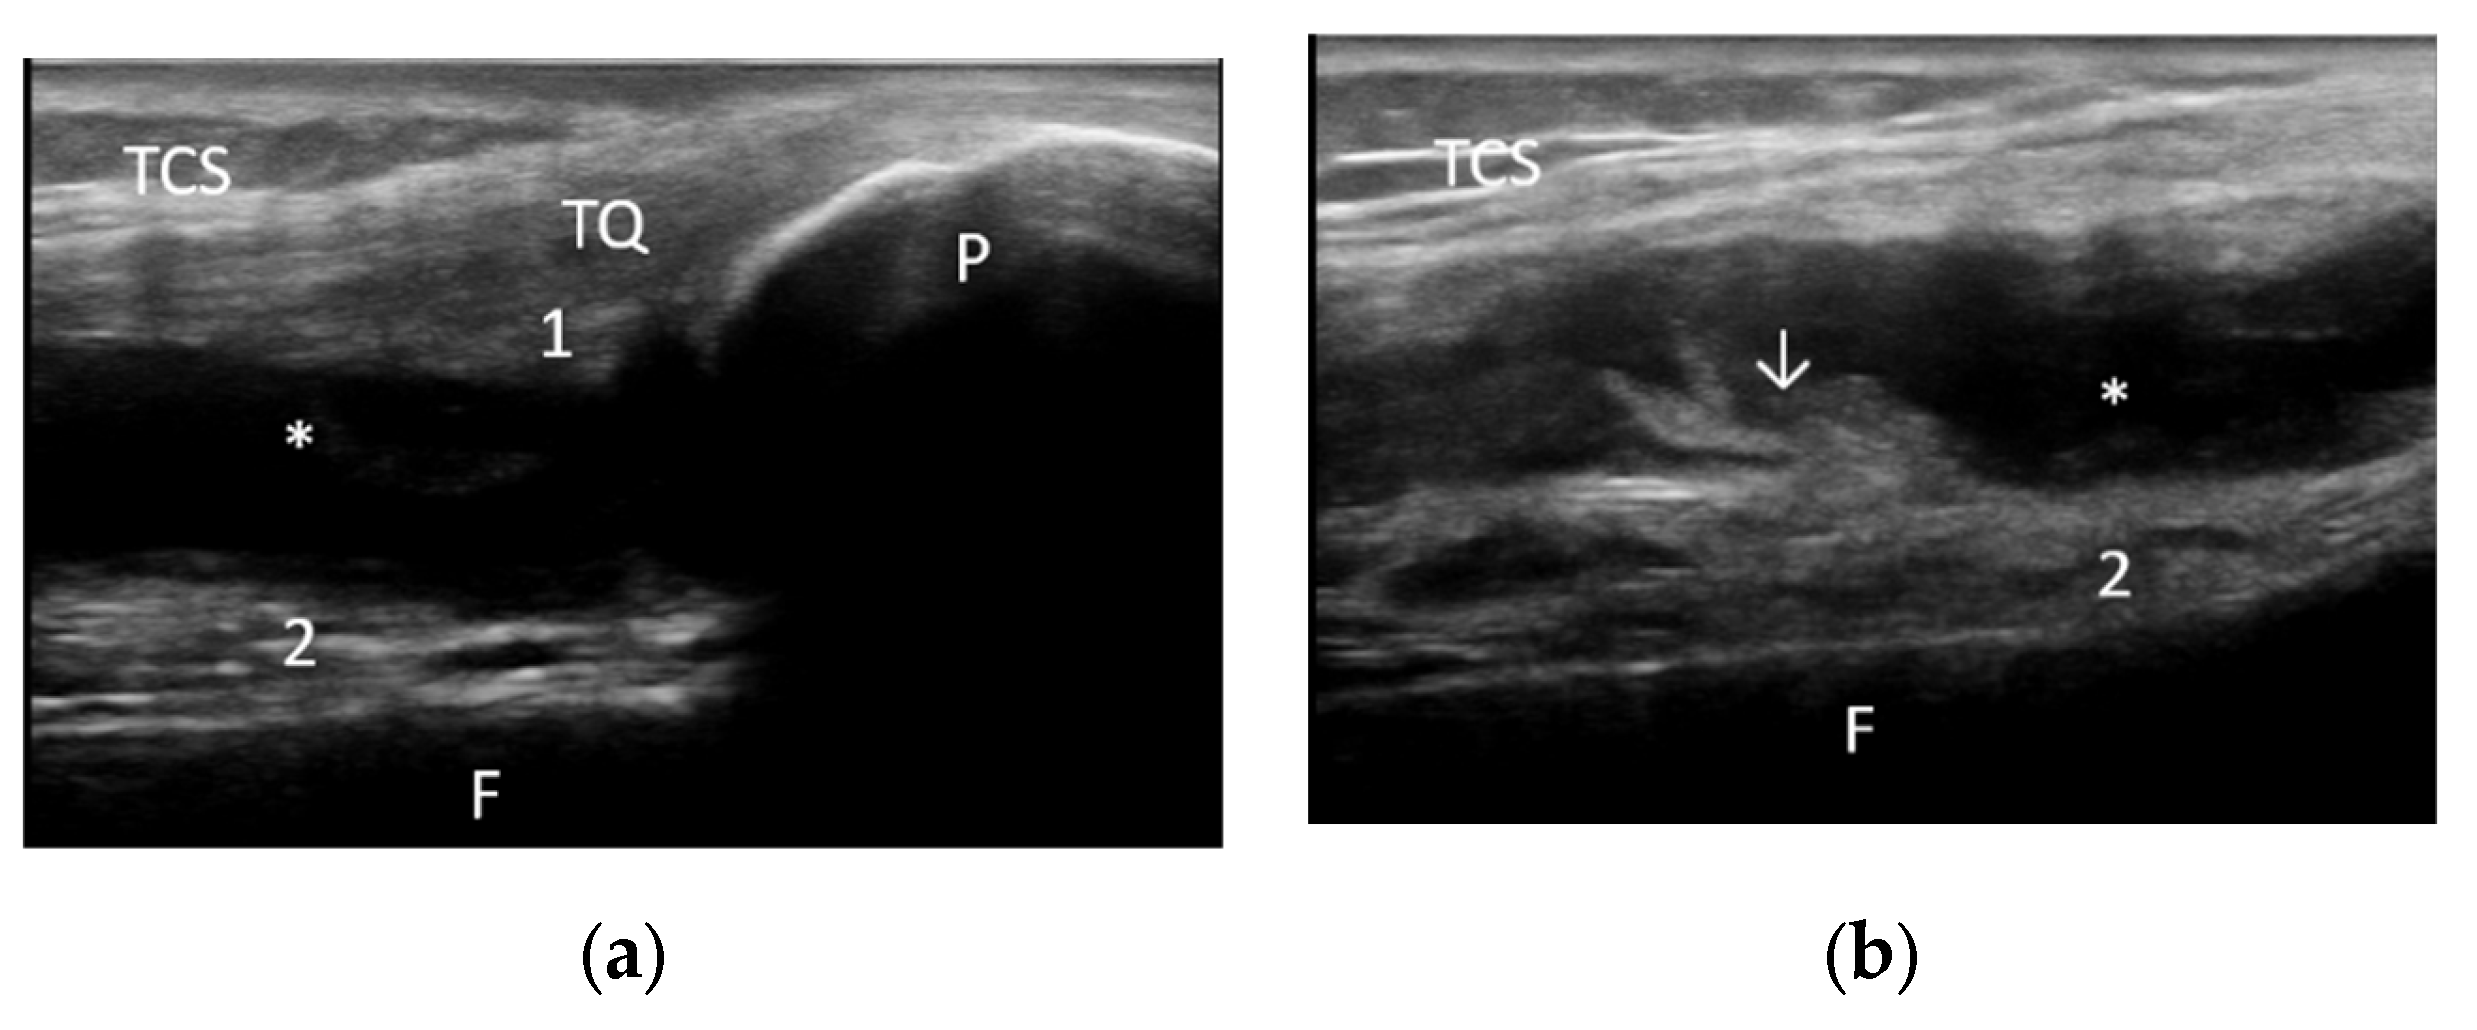

2.2. Demographic Characteristics and Assessment of Clinical, Laboratory and Imaging Data